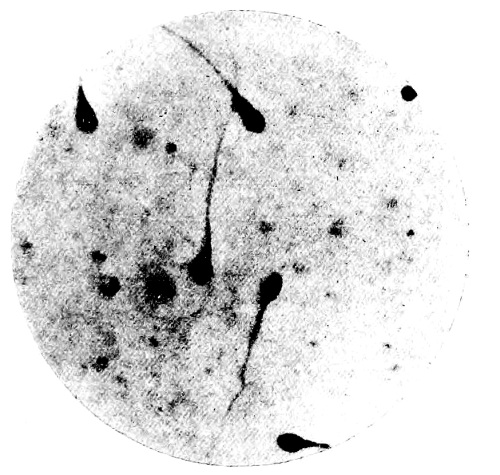

8. Measurement of Blood Corpuscles (human) 97

9. Measurement of Blood Corpuscles (sheep) 97

10. Photo-micrograph of Red Blood Corpuscles from Domestic Fowl 99

11. Photo-micrograph of Blood Corpuscles of Fish 99

12. Photo-micrograph of Blood Corpuscles from a Dried Stain of the Blood of a Cod-fish 100

13. Photo-micrograph of a Frog‘s Blood showing oval nucleated Red Corpuscles 101

14. Photo-micrograph of Crystals of Hæmin 102